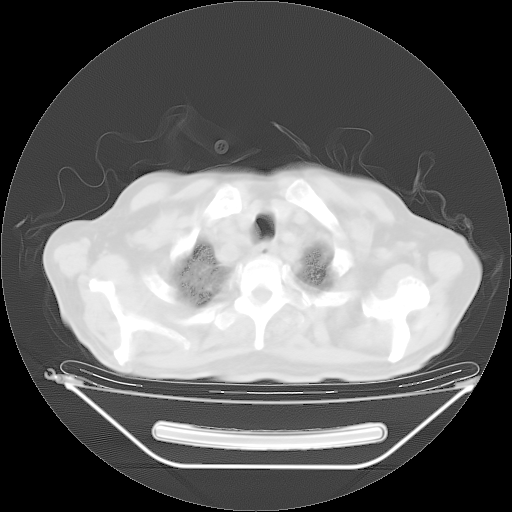

今天复查肺部CT,发现双肺广泛磨玻璃样改变。所以我把3月19日和5月9日相隔50天的肺部CT上传。请大家会诊。

5月9日肺部CT(在4月27日齐鲁医院肺部CT描述部分肺组织磨玻璃样改变,12天后肺组织广泛磨玻璃样改变)

2009年5月9日肺部CT

大致读了系列胸部CT:纵隔窗无明显异常,肺窗:从4、27至今:主要是双肺中下野外带可见毛玻璃样改变,目前处于急性肺泡炎阶段,至于原因考虑1、结替组织或胶原血管性疾病所致?2、恶性疾病如恶组在肺部所致的表现或细支气管肺泡癌?3、药物或其它原因如肺蛋白沉着症所致肺泡炎目前不太可能?总之,明天就去请我院的呼吸科、感染科、血液科和临免专家会诊哈。